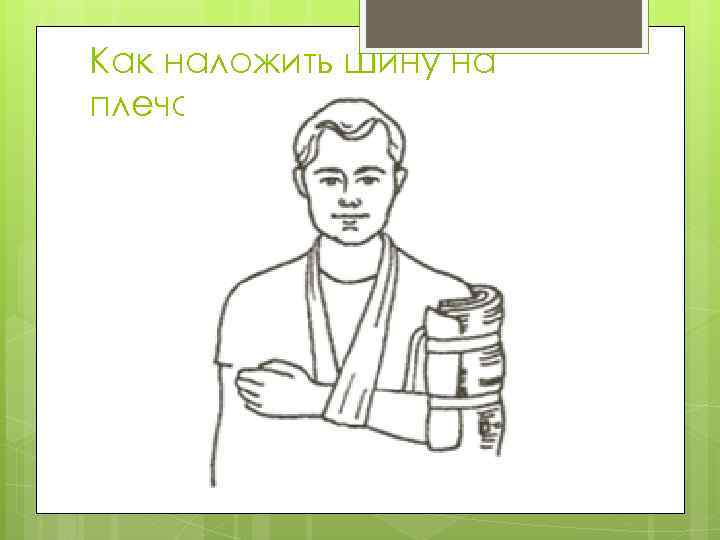

Как наложить шину на плечо? Осторожно разместить сломанную руку сбоку, предплечье — под прямым углом поперек грудной клетки. Шину наложить с внешней стороны руки. Завяжите на шее перевязь для поддержания руки.

Как наложить шину на плечо? Осторожно разместить сломанную руку сбоку, предплечье — под прямым углом поперек грудной клетки. Шину наложить с внешней стороны руки. Завяжите на шее перевязь для поддержания руки.

Как наложить шину на плечо?

Как наложить шину на плечо?